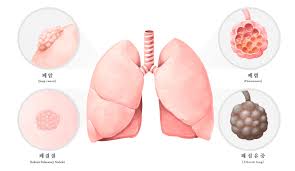

폐결절(pulmonary nodule)은 폐 안에 지름 3cm 이하의 작은 덩어리나 불투명 부위로, 흉부 X‑선이나 CT 검사에서 우연히 발견되는 경우가 많습니다. 대부분은 무증상이며, 양성인 경우가 많지만 일부는 악성(암)일 수 있어 주기적인 관찰이 필요합니다.

🔍 폐결절의 주요 원인

- 감염성 그라뉼로마 (결핵, 진균 감염 등): 폐결절의 약 80% 차지

- 비감염성 염증 (사르코이드증, 자가면역 질환 등)

- 양성 종양 (햄아르토마, 지방종 등)

- 악성 종양 (비소세포폐암, 전이암 등)